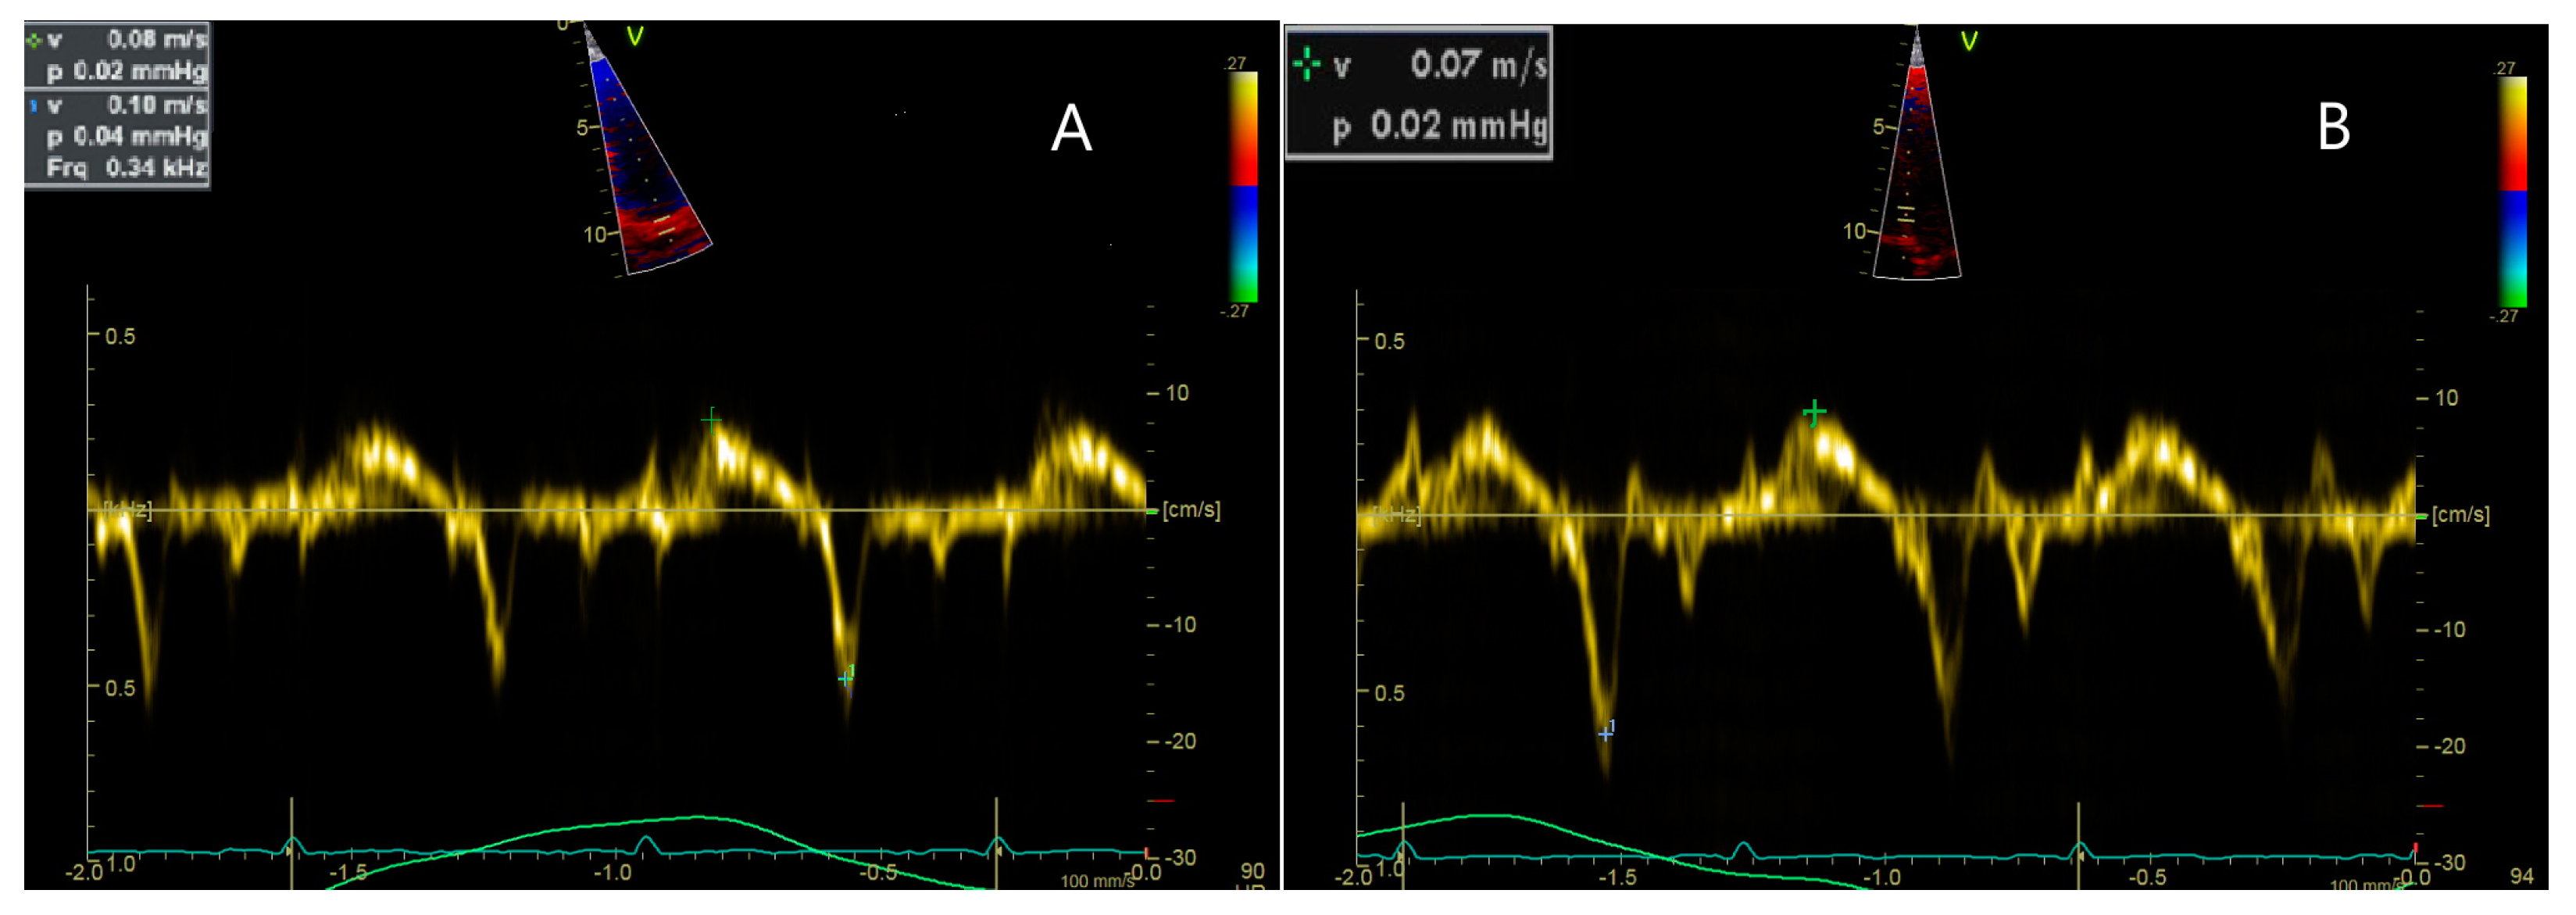

Figure 3.

Cardiac ultrasound, incidence 4 chambers peak systolic (Sa) waves were recorded from the lateral mitral annulus (A, 0.8 cm/s), mitral septal annulus (B, 0.7 cm/s)suggestive of mild LV longitudinal dysfunction.

Initially, no significant changes in cardiac function were observed. However, during a routine evaluation at the age of 3 years and 8 months, a grade I of IV systolic murmur was identified. This finding prompted a detailed cardiological investigation, which revealed signs consistent with cardiomyopathy. Despite the absence of symptoms, the echocardiographic examination confirmed longitudinal dysfunction of the left ventricle (LV) with an ejection fraction (EF) of 56.69%, along with evidence of mild ventricular dilation, as seen in Figure 2 and Figure 3. Additionally, dilated cardiac cavities were observed, with both the right ventricle (RV) and LV measuring 30 mm in size. The ascending aorta measured 11 mm in diameter. The electrocardiogram (EKG) revealed sinus tachycardia (100 bpm), with a QRS axis of 0 degrees and a juvenile ST-T wave pattern.